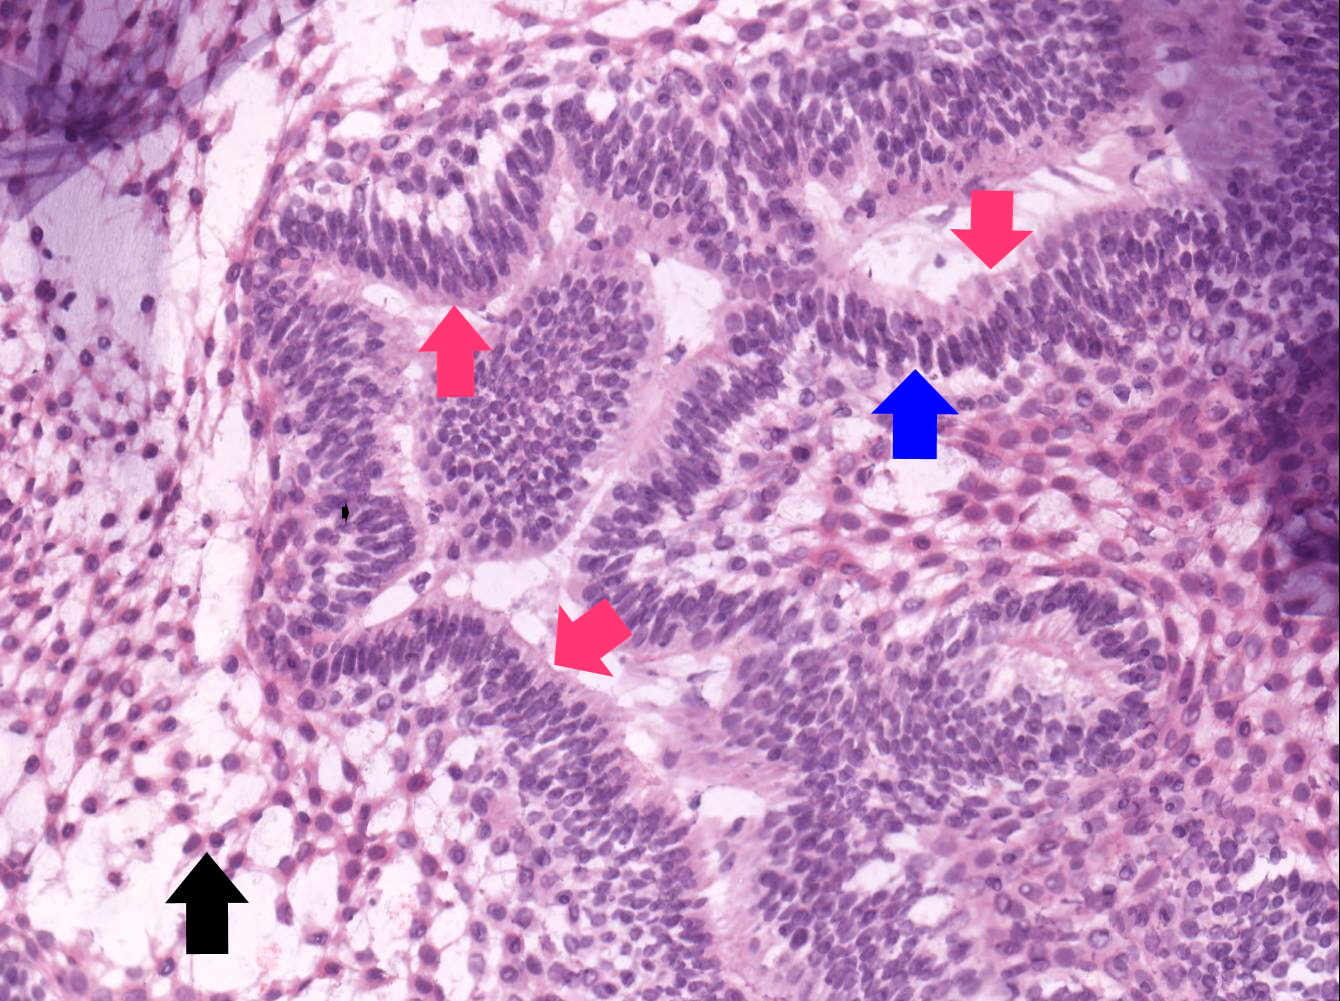

- Follicular: most common subtype; islands of odontogenic epithelium in fibrous connective tissue; may be cystic; classic peripheral palisading and stellate reticulum-like areas

- Plexiform: cords and sheets of anastomosing odontogenic epithelial cells; classic peripheral palisading and reverse polarity not always obvious

- Within the epithelial islands and cords of conventional ameloblastoma and the cystic epithelial lining of unicystic ameloblastoma, the odontogenic epithelium shows similar changes:

- Columnar cells with hyperchromatic nuclei at basal layer, exhibiting peripheral palisading

- Cells show reverse polarization away from basement membrane (Vickers-Gorlin change)

- Subnuclear vacuolization

- Suprabasal cells with a loose, network-like arrangement, recapitulating stellate reticulum formation seen in normal odontogenesis

- No dentin or enamel formation

Contributed by Kelly Magliocca, D.D.S., M.P.H. and Anne C. McLean-Holden, D.M.D., M.S.